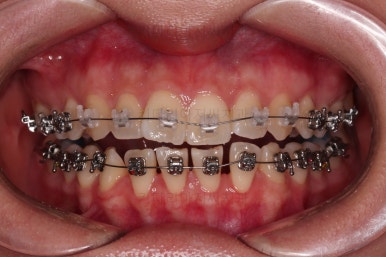

장치를 부착했는데요.

윗니는 웃을 때 더 많이 보이기 때문에 세라믹 장치를 선택하셨고, 아랫니는 거의 안보이는 타입이셔서 메탈장치로 부착을 했습니다.

위아래 둘 다 자가결찰 장치였고요.

동일 회사의 장치였으며 단지 재질만 메탈이냐 세라믹이냐의 차이가 있었던거죠.

이렇게 위아래는 설측이든 뭐든 메탈이든 세라믹이든 마음대로 섞을 수 있습니다.